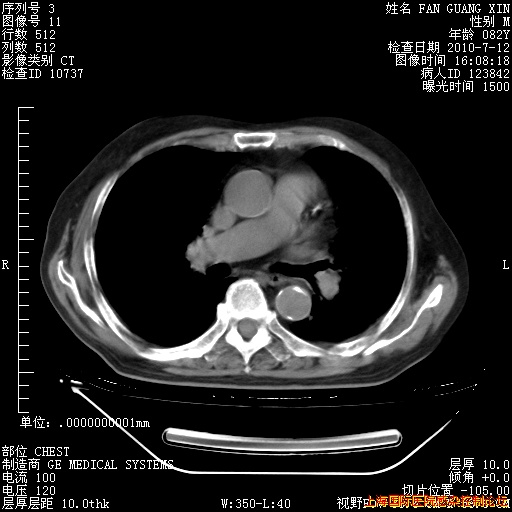

6月12日纵膈窗